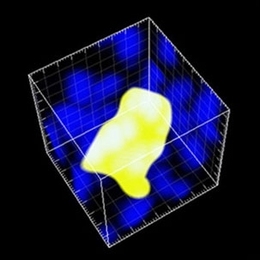

MIT researchers offer glimpse of rare mutant cells Imaging system may help understand origins of cancer July 21, 2008 Read full story →